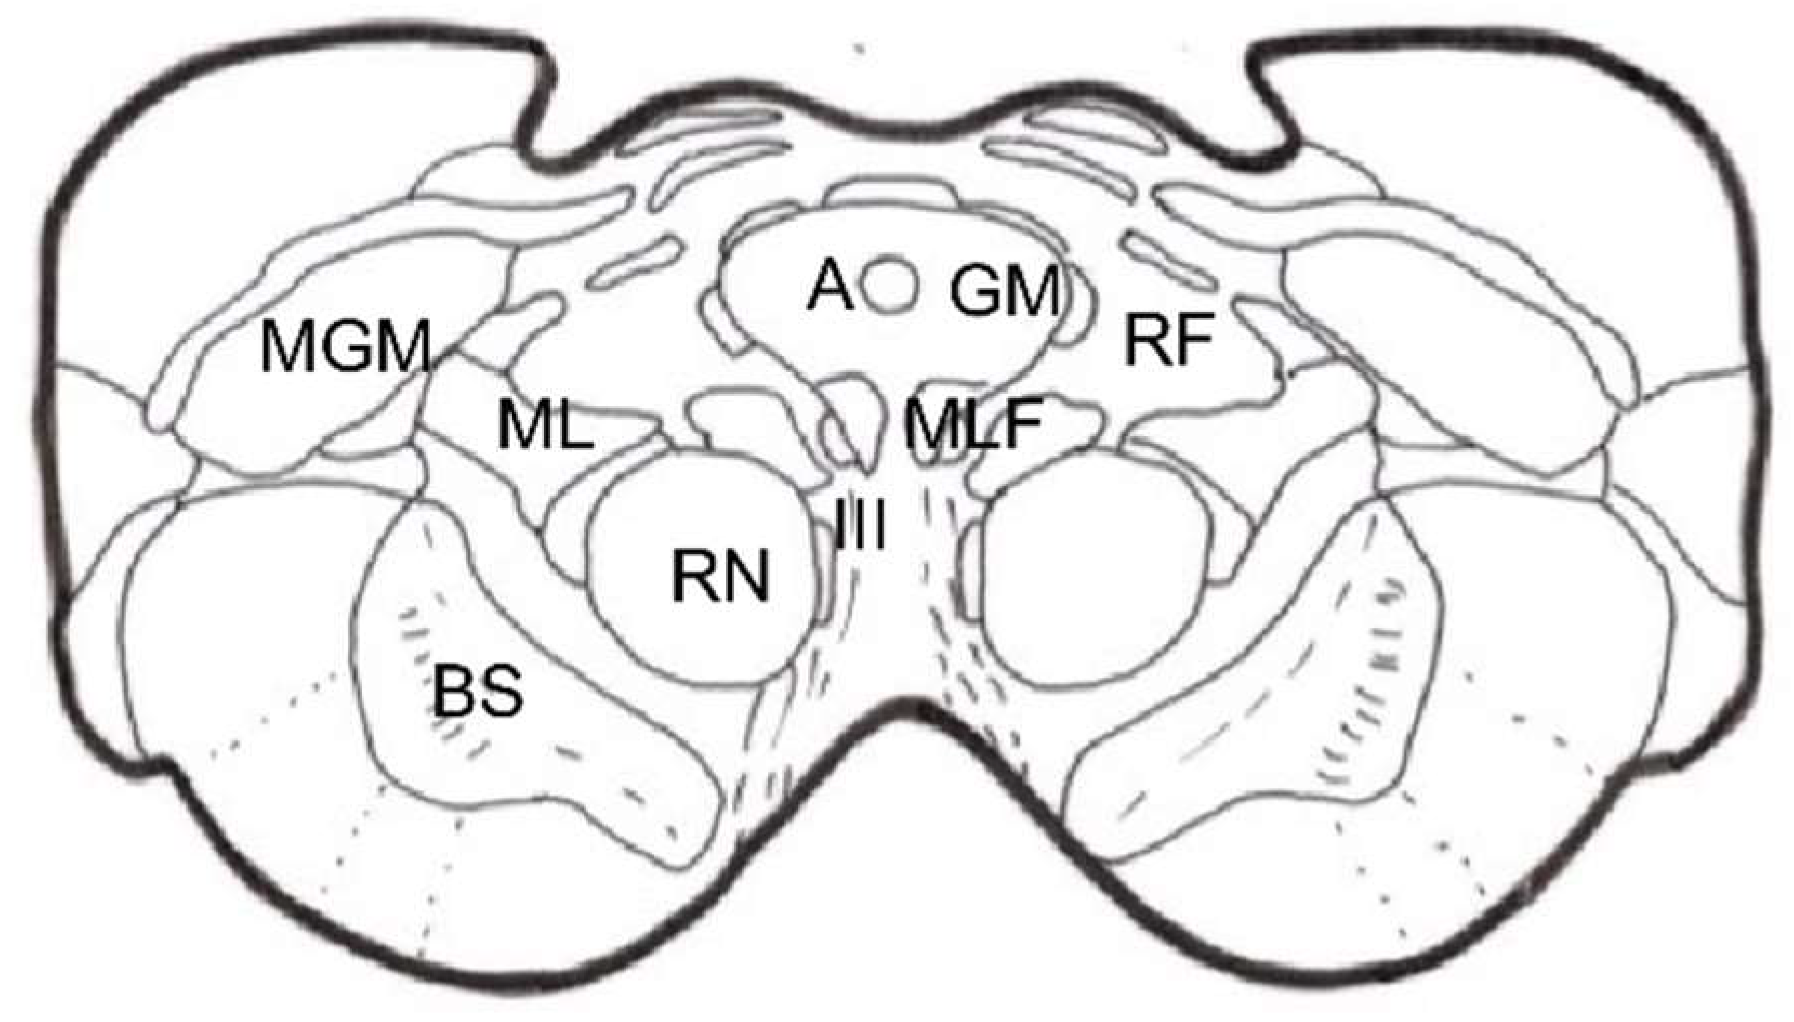

Stereotactic Mesencephalotomy